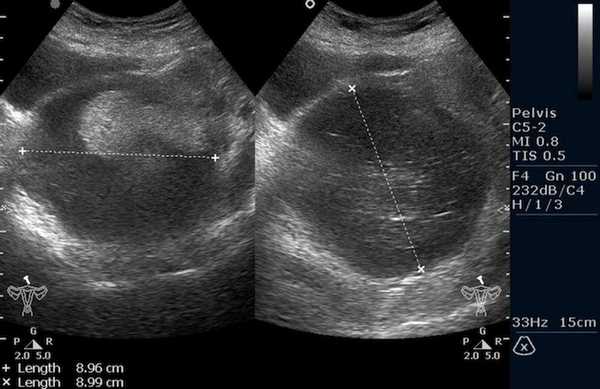

Рисунок 3. - тератома яичника а -УЗИ, б — МРТ.

- УЗИ. «Ультразвук» нужен для того, чтобы выявить первичный очаг как гонадной (в половых органах), так и внегонадной герминогенной опухоли. Его также проводят в ходе терапии, чтобы оценить ее эффективность.

![Тератома яичника (УЗИ малого таза)]()

Тератома яичника (УЗИ малого таза)

Ультразвуковое исследование (УЗИ) мошонки является предпочтительным начальным визуализирующим исследованием для оценки образования яичка. УЗИ может подтвердить наличие новообразования, определить его расположение и оценить состояние противоположного яичка (рис. 4). Чувствительность метода достаточно высокая - от 92 % до 98 %.